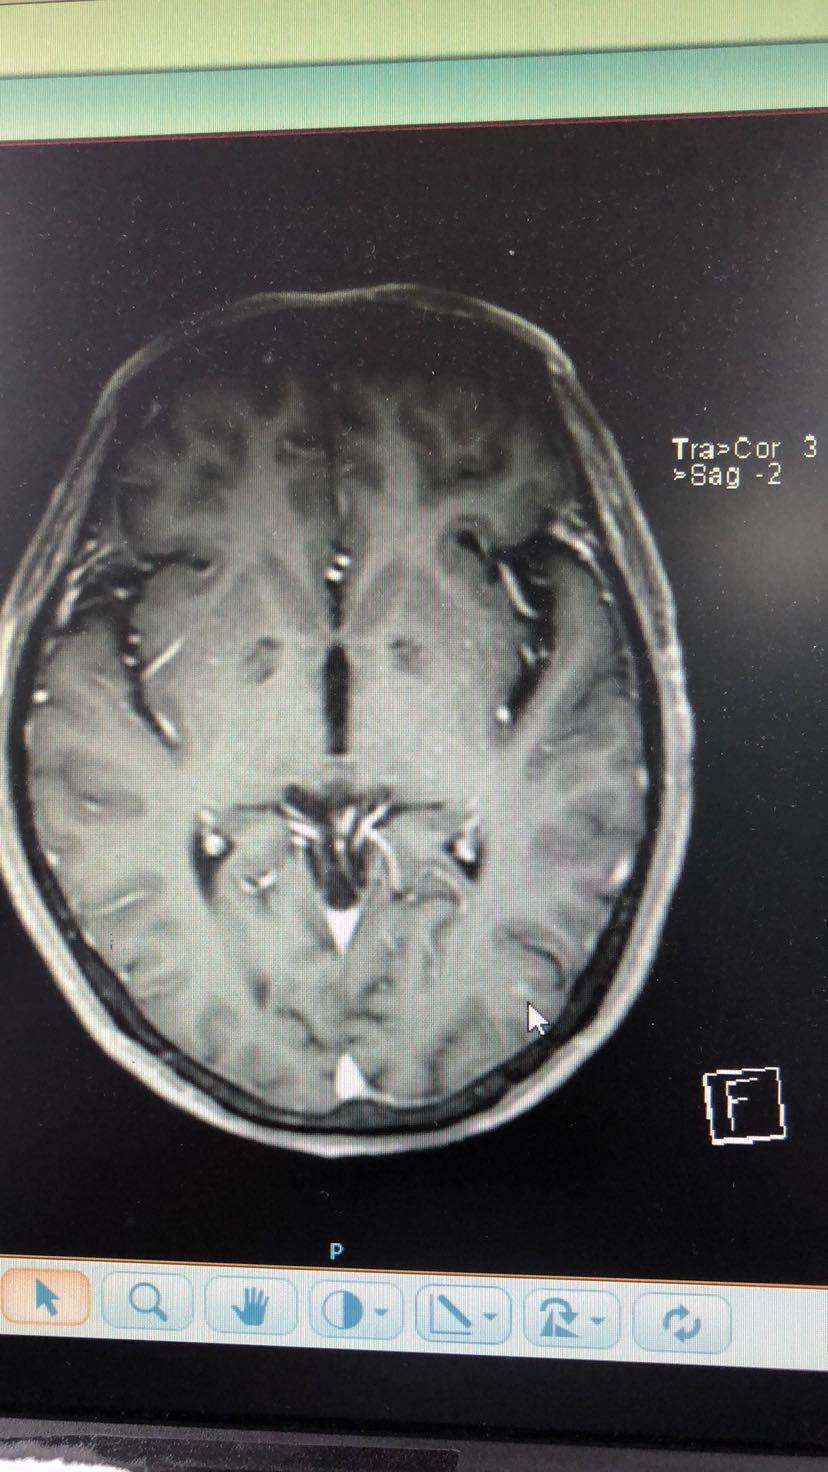

肺鳞癌术后半年怀疑脑转移,哭过之后擦干眼泪继续战斗。求教觅友们,脑部放疗采用哪种方式好?射波刀、伽玛刀、还有立体定向放疗,哪种更好?目前我爸没有脑转症状,一个结节4mm、一个结节2mm,医生建议观察一个月,如果增大就放疗;如果没有变化就继续观察。另外,无基因突变盲试靶向药是选择特罗凯还是9291?我知道阿法替尼是指南规定的鳞癌用药,但阿法替尼入脑效果不好,没用。我家pd-L1表达65%,目前由于放射性肺炎的存在暂时不考虑上pd1。此次脑部放疗后如何预防下一次的脑部复发呢?毕竟放疗治标不治本。另外,求有经验的觅友帮忙看一下脑部核磁影像,看一下鼠标指出的地方是否确为转移瘤。叩谢各位觅友了。